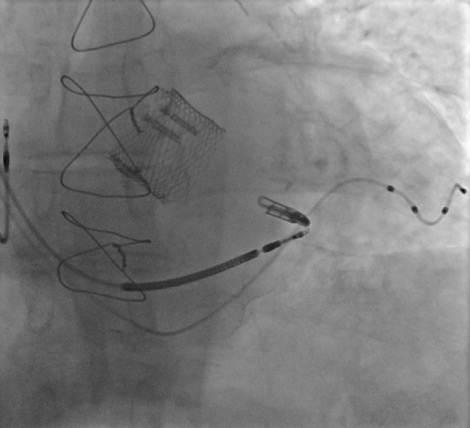

An 81-year-old man with a complex medical history and multiple prior percutaneous interventions, suffering from NYHA class II heart failure and CCS class III treatment-resistant angina, underwent coronary sinus reducer implantation.

Quadripolar CRT + ICD + Lotus Valve + MitraClip + left atrial appendage occluder device.